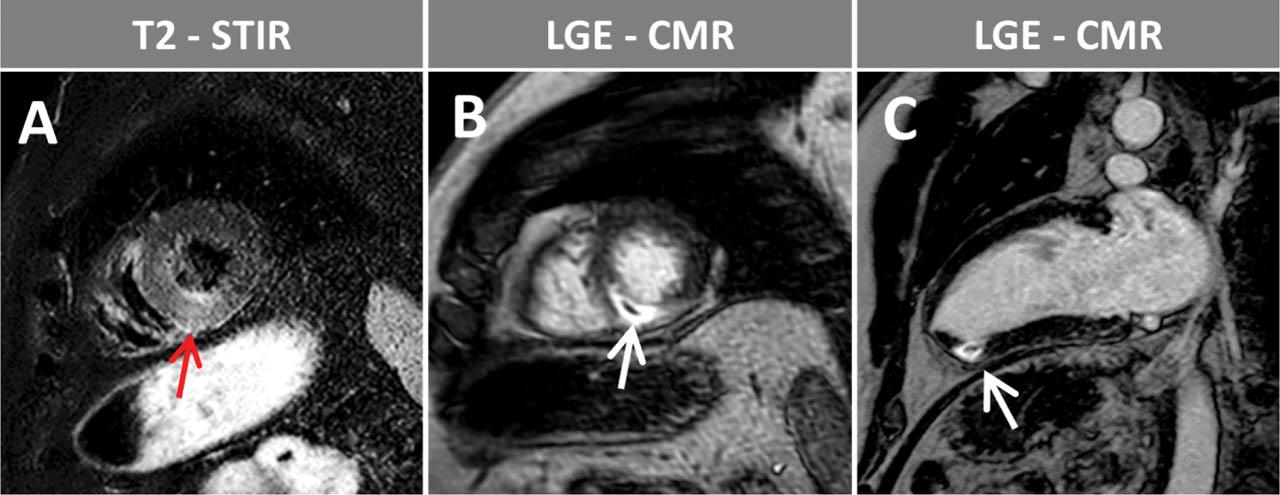

Figure 3

Stress perfusion during adenosine-hyperemia (A, B, C) and LGE images (D, E, F) in a chronic coronary syndrome patient with known two-vessel CAD: chronic total right coronary artery (RCA) occlusion and intermediate circumflex artery (LCX) stenosis as well as a history of lateral myocardial infarction. In the inferoseptal and inferior segments an ischemic scar (white arrow heads) with residual viability at basal, mid-ventricular level (subendocardial LGE with < 50% transmural extent) as well as a transmural inducible perfusion deficit (red arrow heads) exceeding the scar, can be seen, evidence of ischemic, viable myocardium in the RCA territory. On the other hand, the transmural scar (LGE, white arrows) in the lateral wall segments with corresponding perfusion deficit (red arrows) after lateral infarction demonstrates no relevant residual viability in the LCX territory.